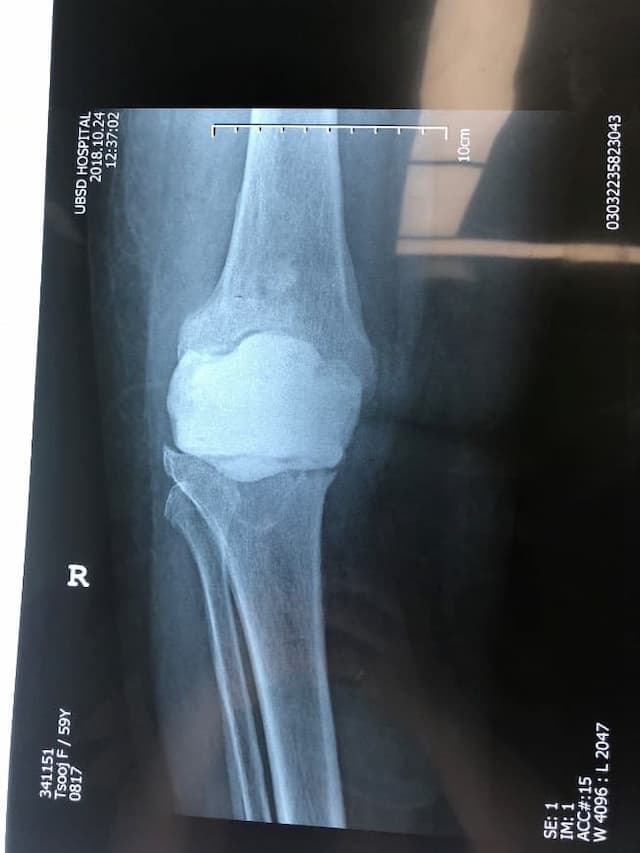

Тохиолдол танилцуулга 4.

Өвчтөн: Б, 73 настай, эмэгтэй

Урьд нь хийгдсэн мэс заслын түүх: 2016 онд өвдөгний хиймэл үе суулгах мэс засал хийлгэсэн. Мэс заслын дараа халдварын хүндрэл гарсан

Хоёрдахь мэс засал: Хиймэл үеийг авч, оронд нь антибиотиктэй цемент хийсэн. Халдварын хүндрэлийн улмаас ясны том хэмжээний дутмагшил үүссэн.

Сэргээн засах мэс засал: Зүүн дунд чөмөг-өвдөгний үе сэргээх тусгай протез суулгах мэс засал.

Үе дайрсан ясны анхдагч хавдар, ясны дутмагшлын үед хийгдэх мэс засалimg17Үе дайрсан ясны анхдагч хавдар, ясны дутмагшлын үед хийгдэх мэс засалimg18

Зураг 1. Сэргээн засах мэс заслын өмнөх рентген зураг. Эгц урд, хажуугаас авсан байдал.